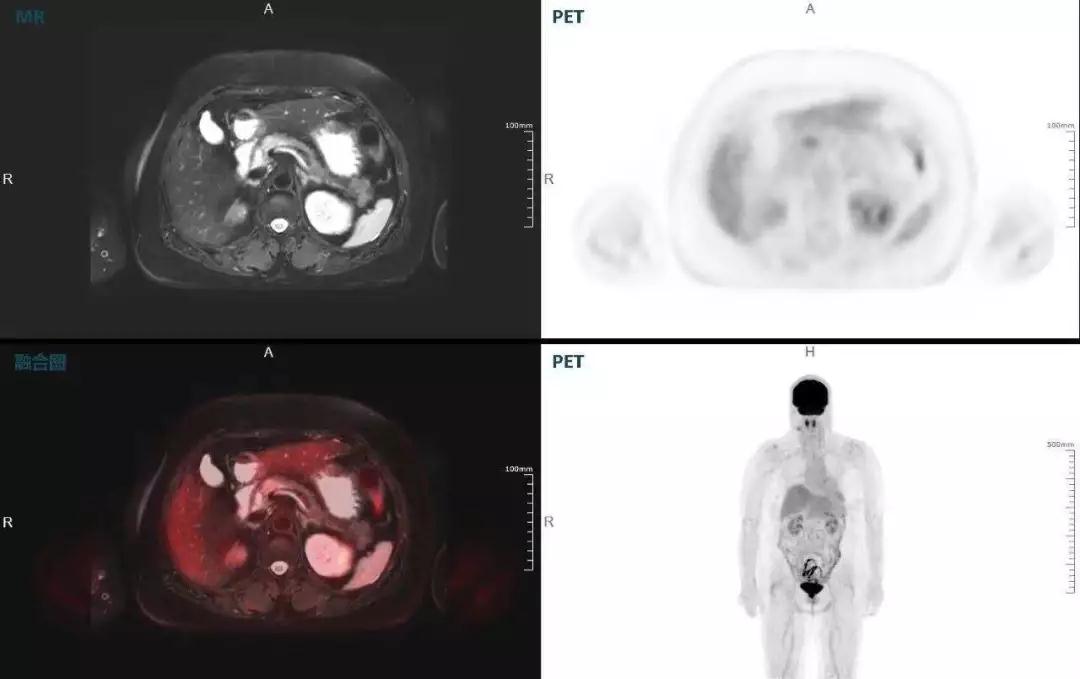

胰腺癌

中山醫(yī)院核醫(yī)學(xué)科在臨床實(shí)踐中發(fā)現(xiàn),基于聯(lián)影“時(shí)空一體”超清TOF PET/MR,不僅解剖信息和代謝信息能夠完美融合呈現(xiàn),同時(shí)精細(xì)展示局部病灶與周?chē)M織的復(fù)雜關(guān)系,并能全盤(pán)檢測(cè)病灶的全身轉(zhuǎn)移,為醫(yī)生臨床診斷提供更豐富信息。

(胰腺腫瘤,MR顯示胰腺體部信號(hào)異常,PET顯示稍高攝取,結(jié)構(gòu)改變和功能異常提示胰腺M(fèi)T可能大。)